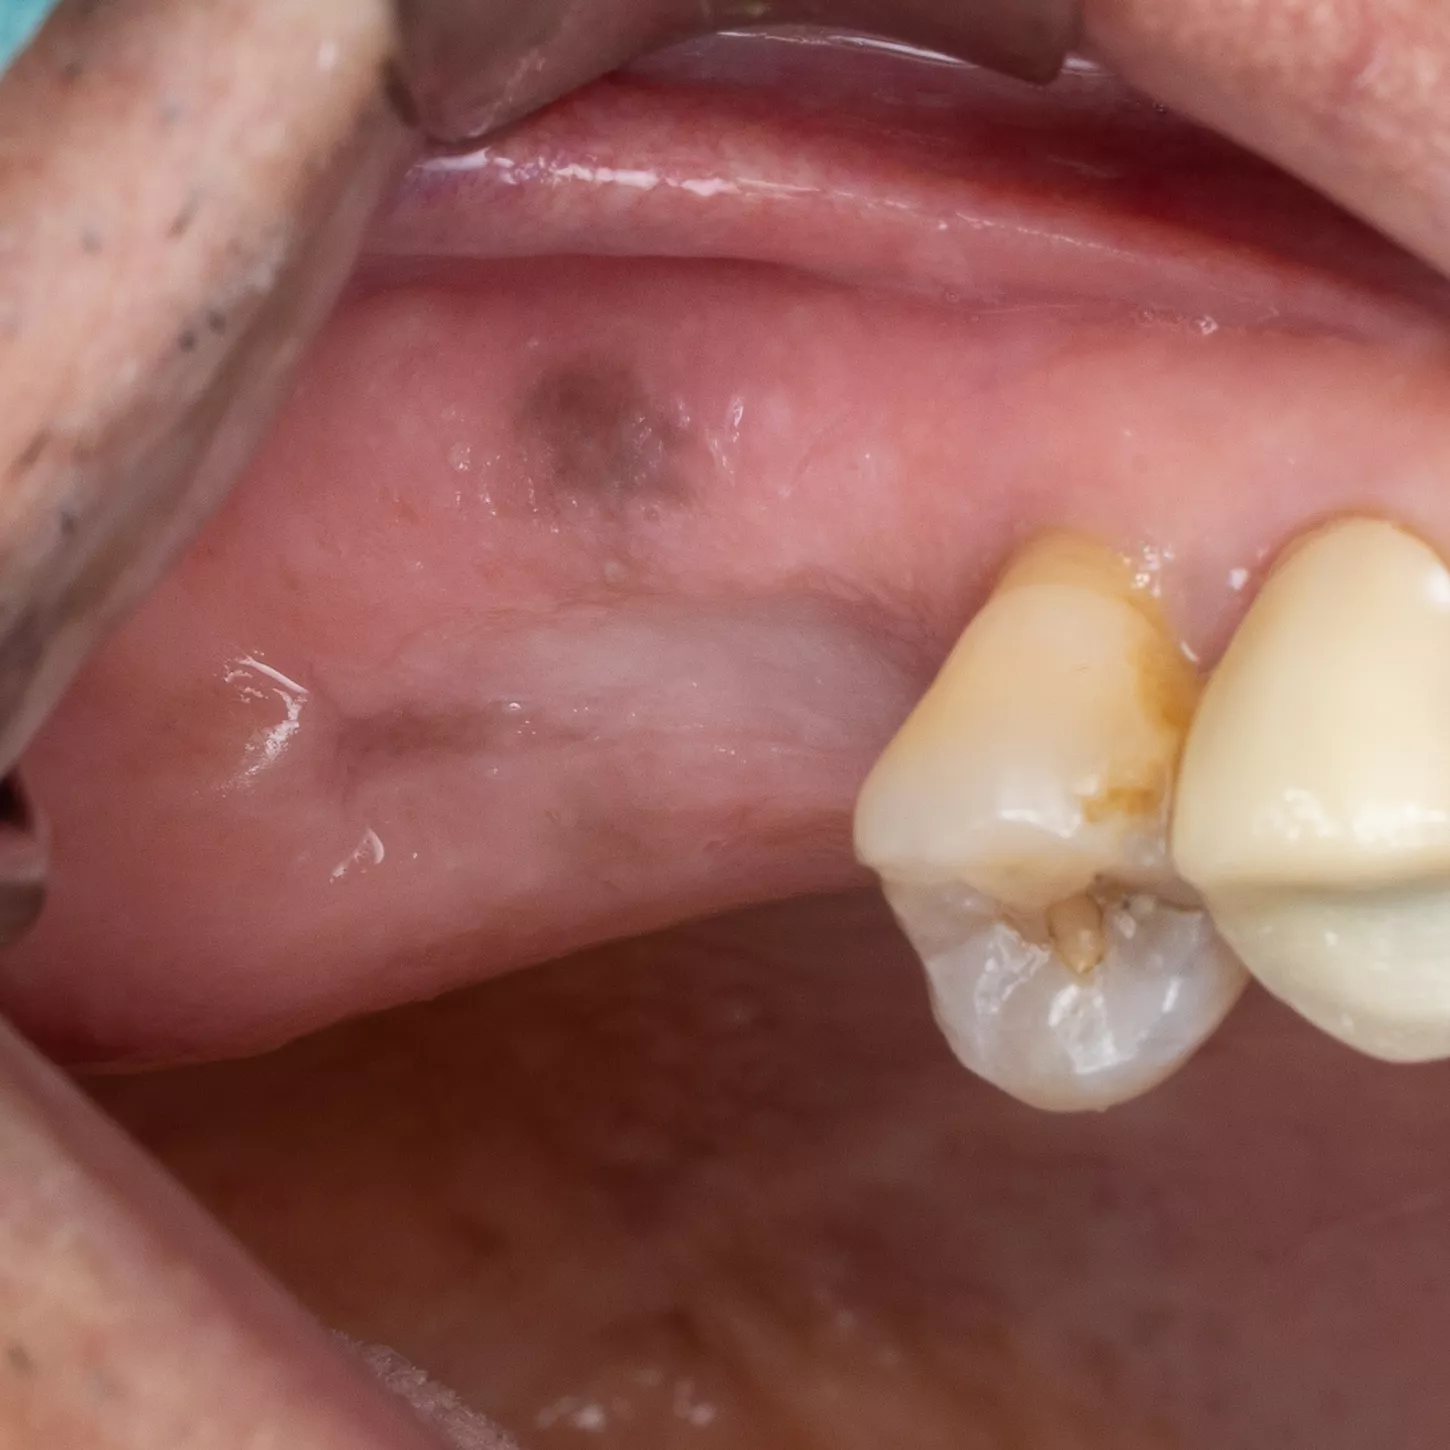

3. Flap detachment:

Crestal incision and diverging vertical discharges. Mucoperiosteal lift.